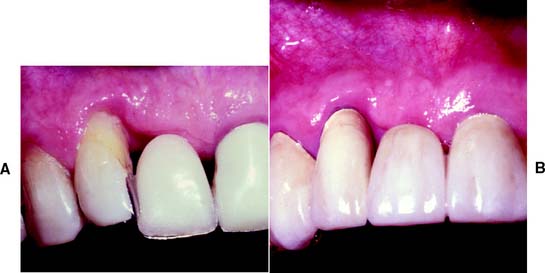

A free (detached) autogenous gingival graft (Fig. 6-13) is used to increase the width of attached gingiva in areas where it is deemed inadequate. The donor site most commonly used is the hard palate, although any area of keratinized tissues, such as an edentulous ridge or the retromolar pad, may be suitable.

Fig. 6-13 Free autogenous gingival graft. A, Planned abutment tooth lacking adequate keratinized gingiva. B, The recipient site is prepared. C, The graft is sutured to place. Some apical adjustment is needed around the premolar before application of the surgical dressing. D, The healed graft. (Compare the width of attached keratinized gingiva here with that in part A.) The defective restoration can be treated at this stage.